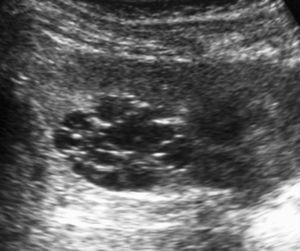

Fig. 7 Tumor rabdoide. Niño de 5 meses con hematuria y masa abdominal. (A) Ecografía abdominal. Corte longitudinal renal izquierdo. Masa sólida, heterogénea (M), bien delimitada en polo inferior de riñón izquierdo. (B) Tomografía computarizada abdominal con contraste intravenoso. Masa renal hipodensa, de aspecto infiltrativo, con crecimiento extrarrenal y tenue captación de contraste. (C) Tomografía computarizada craneal. Masa intraaxial, sólido-quística, fronto-temporal derecha, que desplaza la línea media, con un área de calcificación periférica.